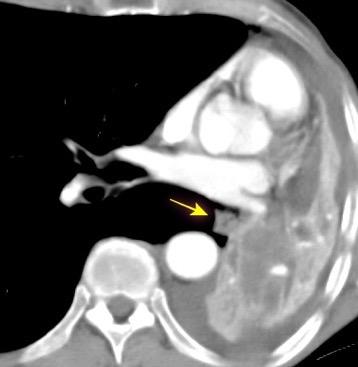

149. TORACOABDOMINAL: GANGLIOS

150. TORACOABDOMINAL: S SEUDOQUISTE PANCREÁTICO